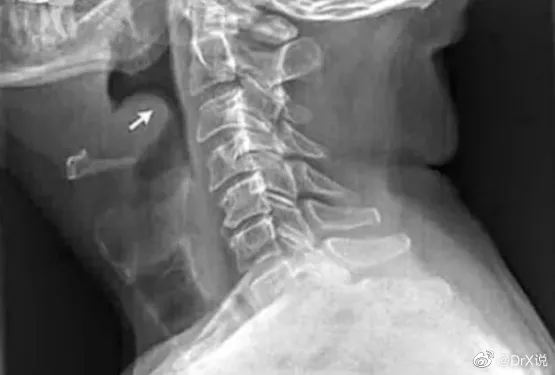

根據「DrX說」文章中指出,喉科醫生表示,死者是急性會厭炎引發急性上呼吸道阻塞而窒息。醫生推測,可能是死者前一天晚上吃火鍋時,高溫辛辣刺激,導致會厭出現發炎水腫症狀,再加上冰冷飲料的刺激之下,腫脹的情況加劇,由於症狀一開始跟普通的喉嚨發炎相似,誤以為是扁桃體發炎、喉嚨發炎或者感冒,錯過黃金急救時間,導致患者憋死。

導致急性會厭炎的原因,包括:受到細菌或病毒感染,相鄰器官感染,或者受到外力創傷,像是吸入高熱飲品以及有害氣體,異物刺入等,會厭也會受到損害。醫師強調,急性會厭炎會出現吞嚥劇烈疼痛感,呼吸困難,聲音沙啞、呼吸喘等,以及頭痛、精神萎靡、畏寒發燒等全身症狀,幾個小時內就會造成呼吸道阻塞,影響呼吸,因此一旦出現以上症狀,就要盡快就醫。